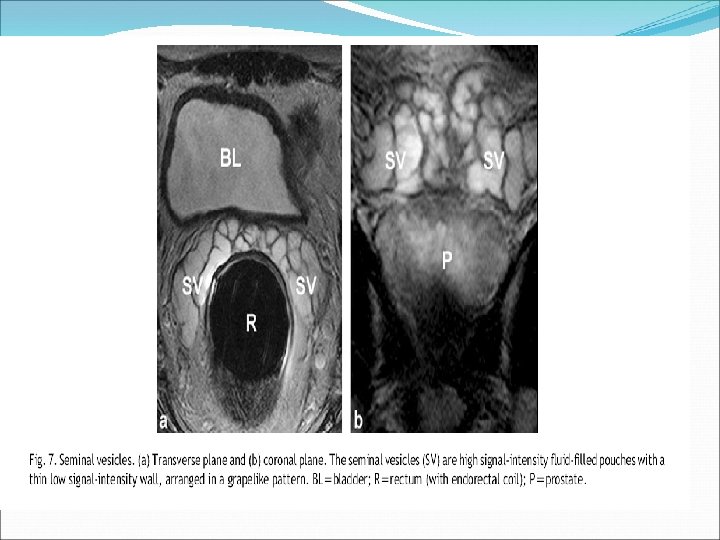

Seminal vesicles • located superior to the base of the prostate. • They undergo confluence with the vas deferens on each side to form the ejaculatory ducts. The ejaculatory duct complex consists of the two ejaculatory ducts along with a second loose stroma rich in vascular spaces. • The utricle (when present) is located between the ejaculatory ducts. The remnants of the utricle occasionally form cystic structures in the midline posteriorly. • The seminal vesicles are resistant to nearly all of the disease processes that affect the prostate. Seminal vesicle involvement (SVI) by prostate cancer (PCa) is one of the most important predictors for PCa progression